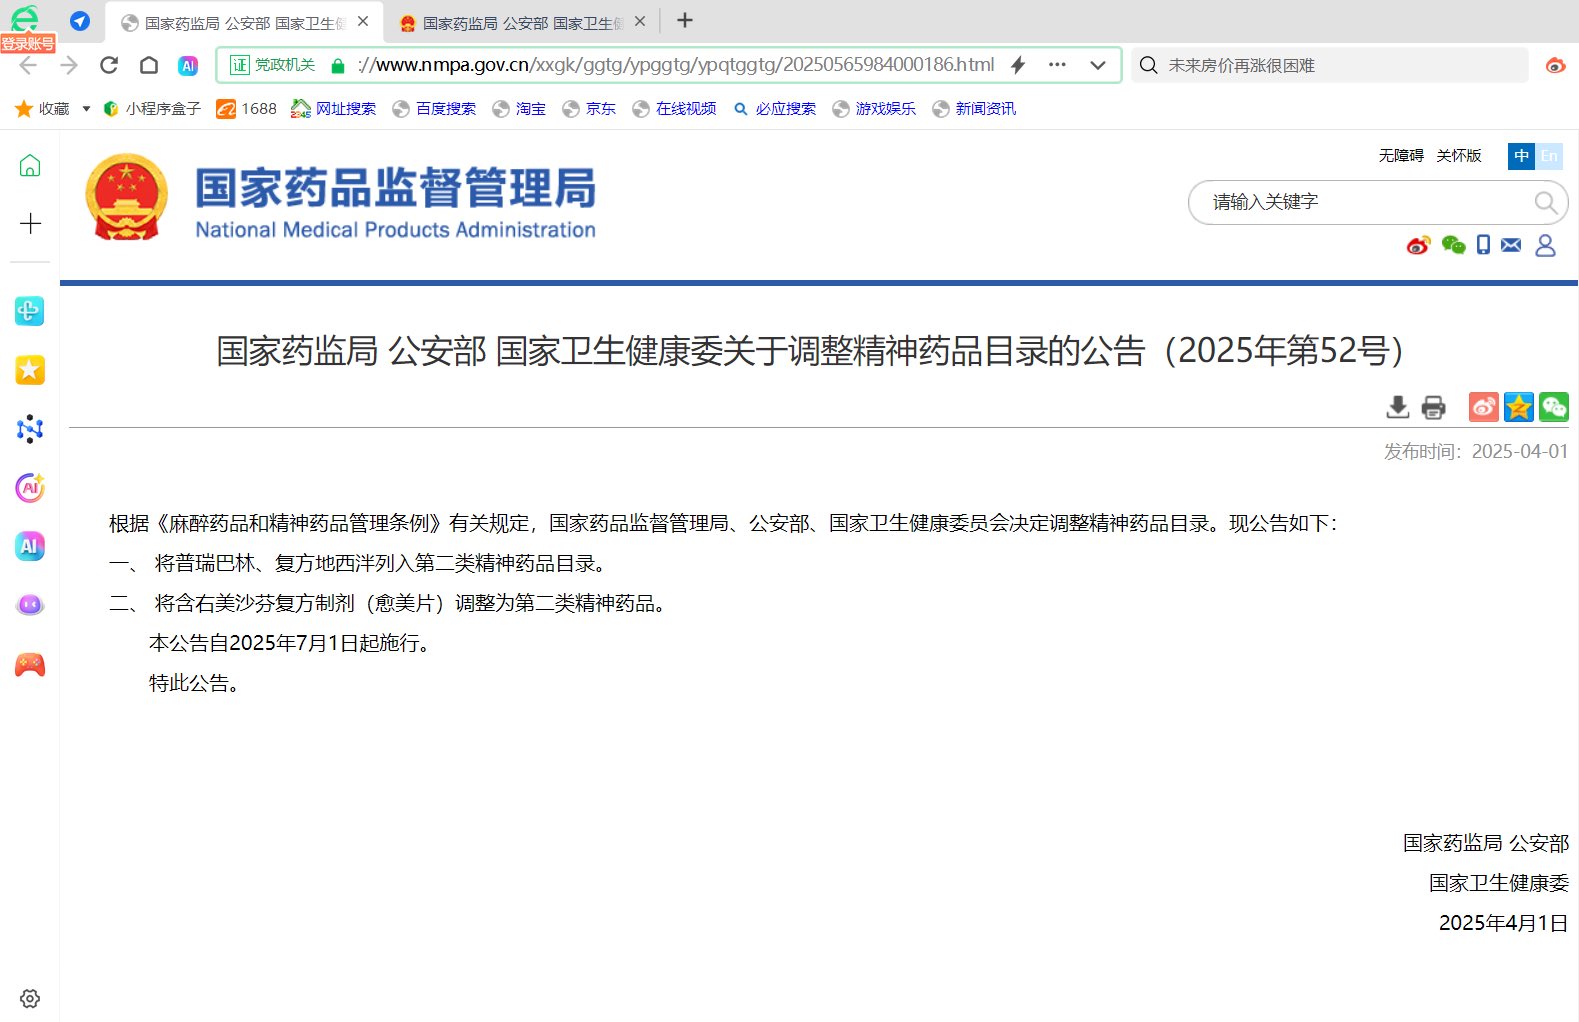

猫,诗歌,精神动力学。艺术,朝闻道,波粒二象性。不断寻找着广播塔的星际候鸟。 | “我们彻夜飞旋,直至没入火焰。” | 倒影@TauCeti_10700 计划这个号机的浓度更高一些 | 🚪88/158